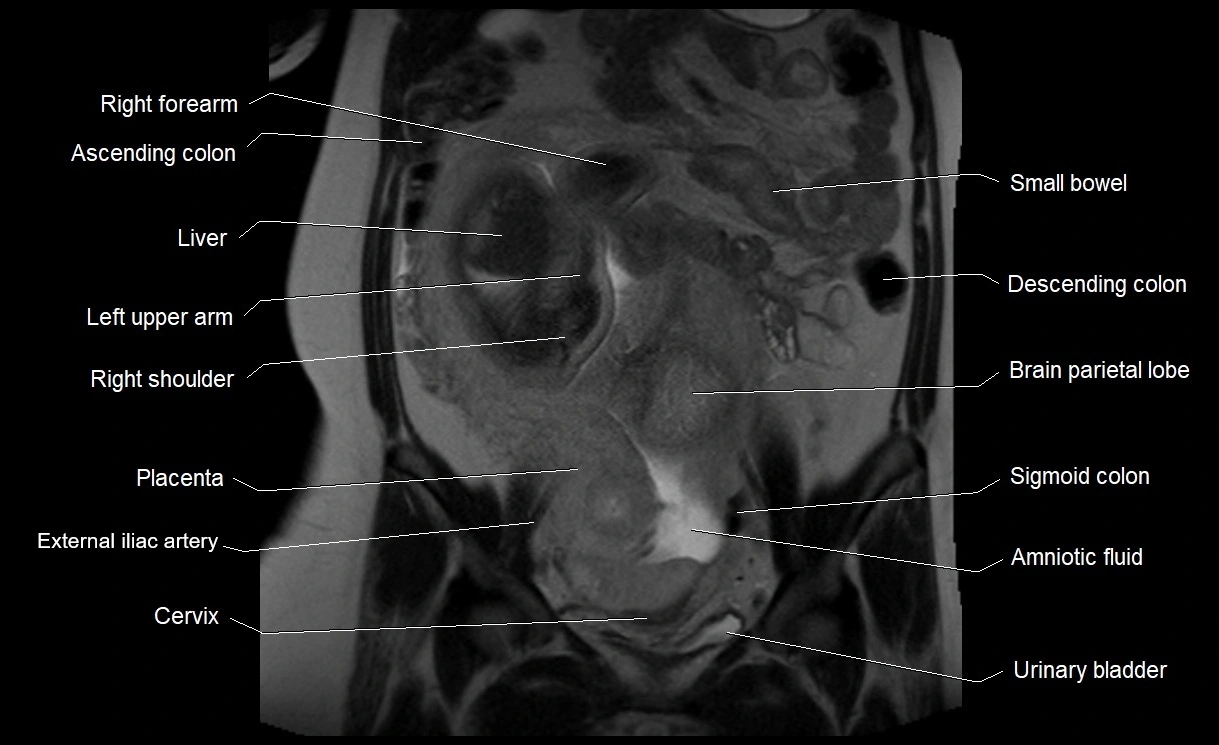

MRI Appearance

T2 HASTE (T2 GRE):

• Amniotic fluid shows very bright hyperintense signal

• Provides natural contrast against fetus and placenta

• Small particles (vernix) may appear as scattered hypointense foci within bright fluid

T1 GRE:

• Amniotic fluid shows low signal intensity (dark)

• Hemorrhage, infection, or proteinaceous content may cause focal or diffuse high signal intensity

MRI image

image